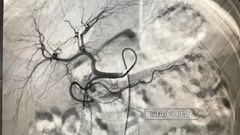

VHO- Bé Chung Ngọc T. (sinh năm 2013, Cao Bằng) được phát hiện mắc bệnh vẩy nến từ lúc mới 2 tháng tuổi, nhưng không được chữa trị triệt để, cộng với gia đình tắm lá khiến bé bị mụn mủ toàn thân, da bong tróc thành mảng lớn.